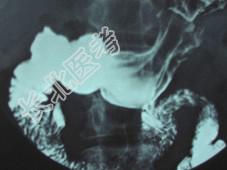

- 单项选择题女,23岁, 上腹部疼痛半月,消化不良, X线检查如图,可能的诊断为 ( )

A、十二指肠球部溃疡

B、十二指肠憩室

C、胃窦炎

D、十二指肠癌

E、十二指肠淤积症